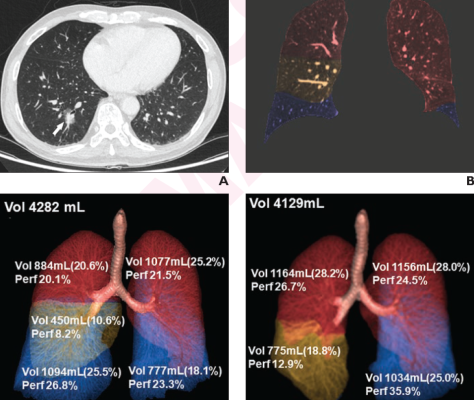

76-year-old male patient who underwent right lower lobectomy for lung cancer. (A) Axial image from preop DECT chest exam shows 2.3-cm part-solid nodule in right lower lobe (arrow). Nodule confirmed to represent lung adenocarcinoma, based on pathologic assessment of surgical specimen. (B) Monochromatic image at 70-KeV with color overlay shows segmentation of five pulmonary lobes. Red indicates upper lobes; yellow indicates right middle lobe; and blue indicates lower lobe. 3D volume-rendering images from (C) preop and (D) 6-month postop DECT show volume, volume ratio, and perfusion ratio for each lobe; ratios computed with respect to entire lung. Values used to compute postop changes in lung volume ratio and lung perfusion ratio for each lobe.

In this AJR accepted manuscript, 81 patients (38 men, 43 women; mean age, 60.5 years; lobectomy in 43, limited resection in 38) awaiting lung cancer resection surgery between March 2019 and February 2020 were included. Patients underwent thoracic DECT and PFT evaluation preoperatively and 6 months postoperatively. Pulmonary lobes were segmented, and lobar volume and perfusion ratios—both relative to whole-lung values—were computed. Perfusion measures reflected DECT-derived iodine content. Patients then completed 6-month postoperative quality-of-life questionnaires.

Ultimately, lung perfusion ratio increases were greater after lobectomy than limited resection for ipsilateral nonresectedlobe(s) (39.9±20.7% vs 22.8±17.8%) and contralateral lung (20.9±9.4% vs 4.3±5.6%). After right lower lobe lobectomy, the largest postoperative increases in lung volume ratio occurred in the right middle lobe (44.1±21.0%), whereas the largest postoperative increase in lung perfusion ratio occurred in the left lower lobe (53.9±8.6%).